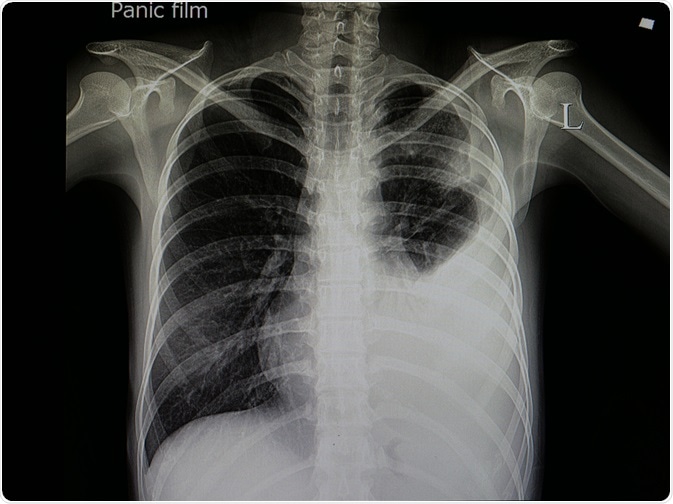

An X-ray or CT scan of the chest is usually done to visualize the location and severity of the inflammation in the lungs. In a chest x-ray, certain characteristics that can be used to differentially diagnose viral pneumonia include interstitial infiltrates, bilateral infiltrates, and patchy distribution of interstitial infiltrates. Moreover, thin-section thoracic CT is particularly important for detecting specific features of viral pneumonia.

Chest X-Ray

Image Credit: create jobs 51/Shutterstock.com